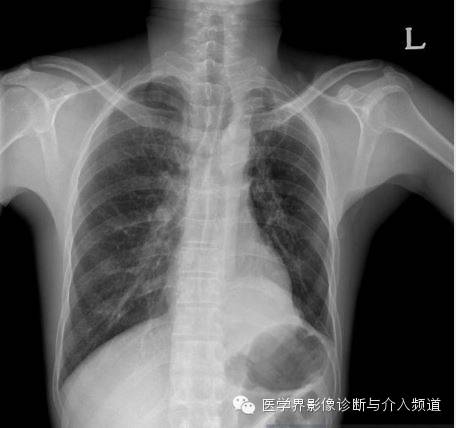

男,47岁,拍胸片发现异常。

既往史:13年前行左肺上叶肺减容术。

胸片示左下胸腔一肿块影。CT增强示左肺下叶一低密度肿块,其内可见高密度影,PET-CT示肿块边缘FDG摄取增加,肿块中央摄取减低。